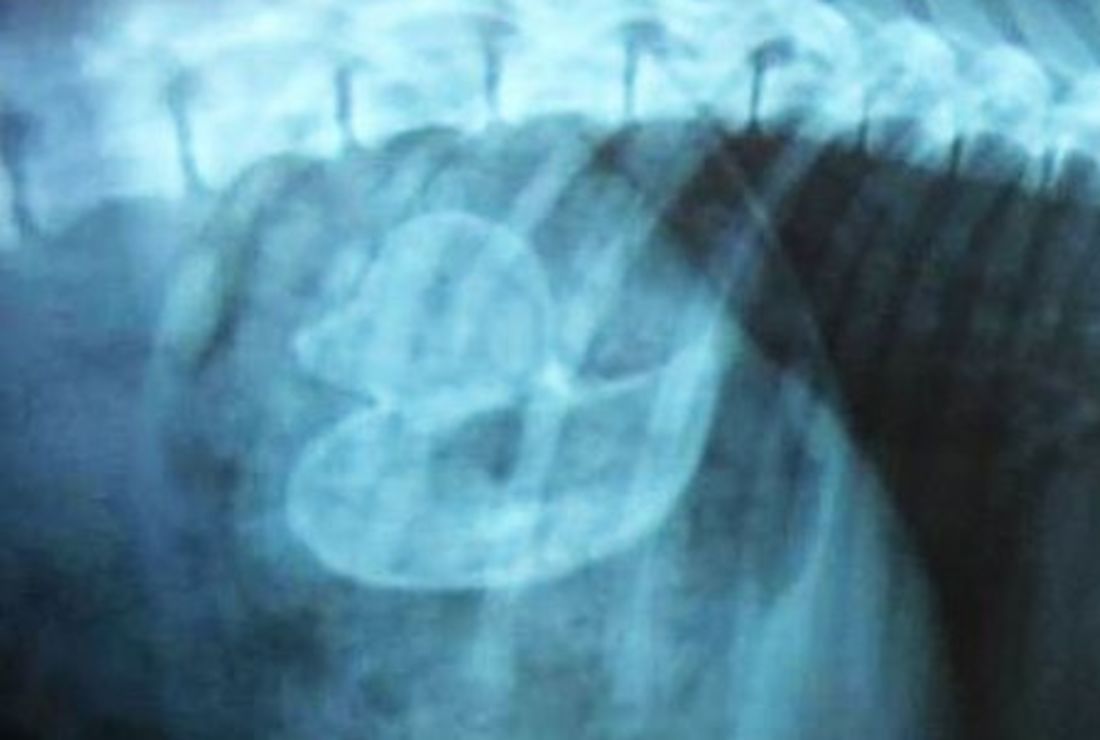

Удаление инородных тел из кишечника

Удаление инородных тел из кишечника 115 фотографий